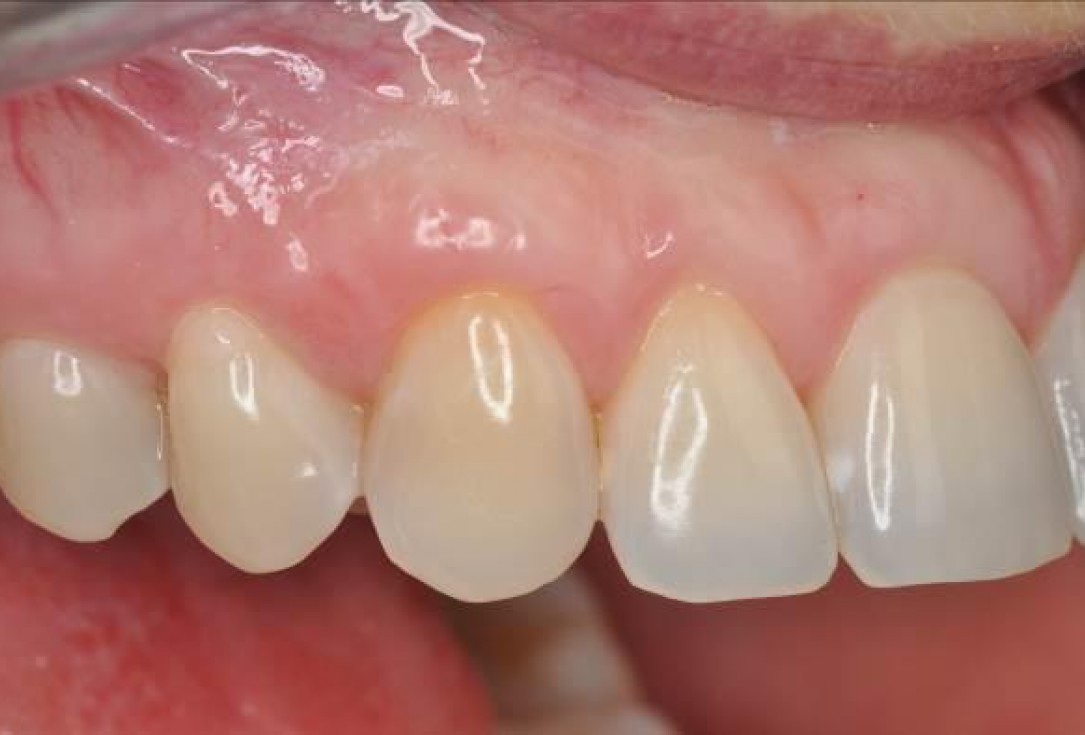

06/06 - Clinical situation 5 months post-operative.Multiple gingival recessions treated with the modified coronally advanced flap in conjunction with mucoderm® and Straumann® Emdogain® - Dr. D. B. Hangyási